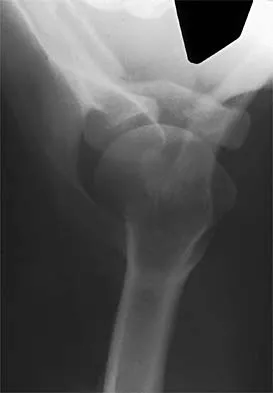

A 10-year-old girl has a right elbow deformity that is the result of trauma 5 years ago. She has no pain despite the arm deformity. The radiographs in Figures 42a and 42b show complete healing. This radiographic appearance demonstrates what complication?

Detailed Explanation